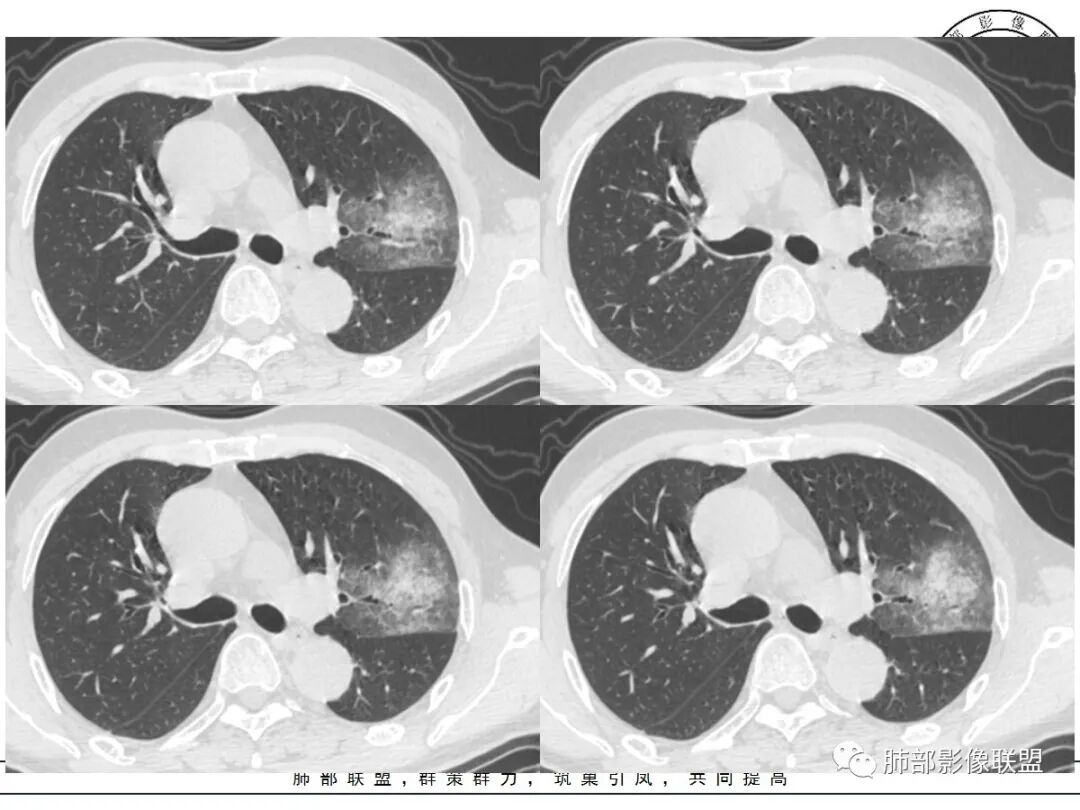

1、团片状,实行密度区外观整体圆顿,位于上叶尖后段与下舌段区间。局部膨隆,但未见分叶,肿瘤多见。

2、偏心空腔病灶,气腔略呈新月形,壁不规则,腔内结节相对密实,明显强化且不均,支持新生物而非曲菌球等。炎性空洞多有强化环。

3、病变强化较明显,其内隐约显示多发小斑片状无强化灶,可疑边界不清小灶坏死区。病灶内血管影浅淡、模糊不规则。

4、支气管改变:上舌段支气管远段延入部分稍示僵硬。尖后段见分支支气管阻塞,恶性多见。

5、周围磨玻璃,3个月后逐渐转为密实,应符合当初附壁生长为主,且逐渐向实体成分转换。

6、病变长轴平行且受限于胸膜,外围大内带小,符合外朝内发展病变。“腔内结节状明显强化”加之支气管改变有力支持新生物诊断。如此大范围边界不清的磨玻璃影让人浮想联翩。如此大范围病灶,肺门纵隔未见肿大淋巴结也让人意外。